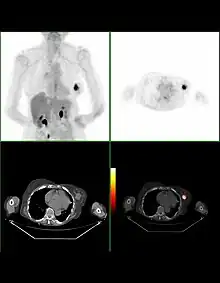

Bilan d'extension

La recherche de métastases est fondamentale dans la stratégie du traitement du cancer du sein. Mais, malgré les nombreuses études réalisées ou la connaissance approfondie de certaines explorations, il n'existe actuellement aucune stratégie validée de recherche systématique de métastase dans le cancer du sein.

La plupart des recommandations proposent actuellement un bilan d'extension comportant un examen clinique soigneux à la recherche de métastases ganglionnaires, une radiographie thoracique, une échographie hépatique et une scintigraphie osseuse. Pour les tumeurs de très petite taille, ce bilan peut être facultatif. En revanche, pour les tumeurs évoluées (tumeurs inflammatoires, multifocales, envahissement ganglionnaire important), le risque métastatique initial est élevé et peut justifier un bilan plus poussé comportant une tomodensitométrie corps entier et une IRM mammaire.